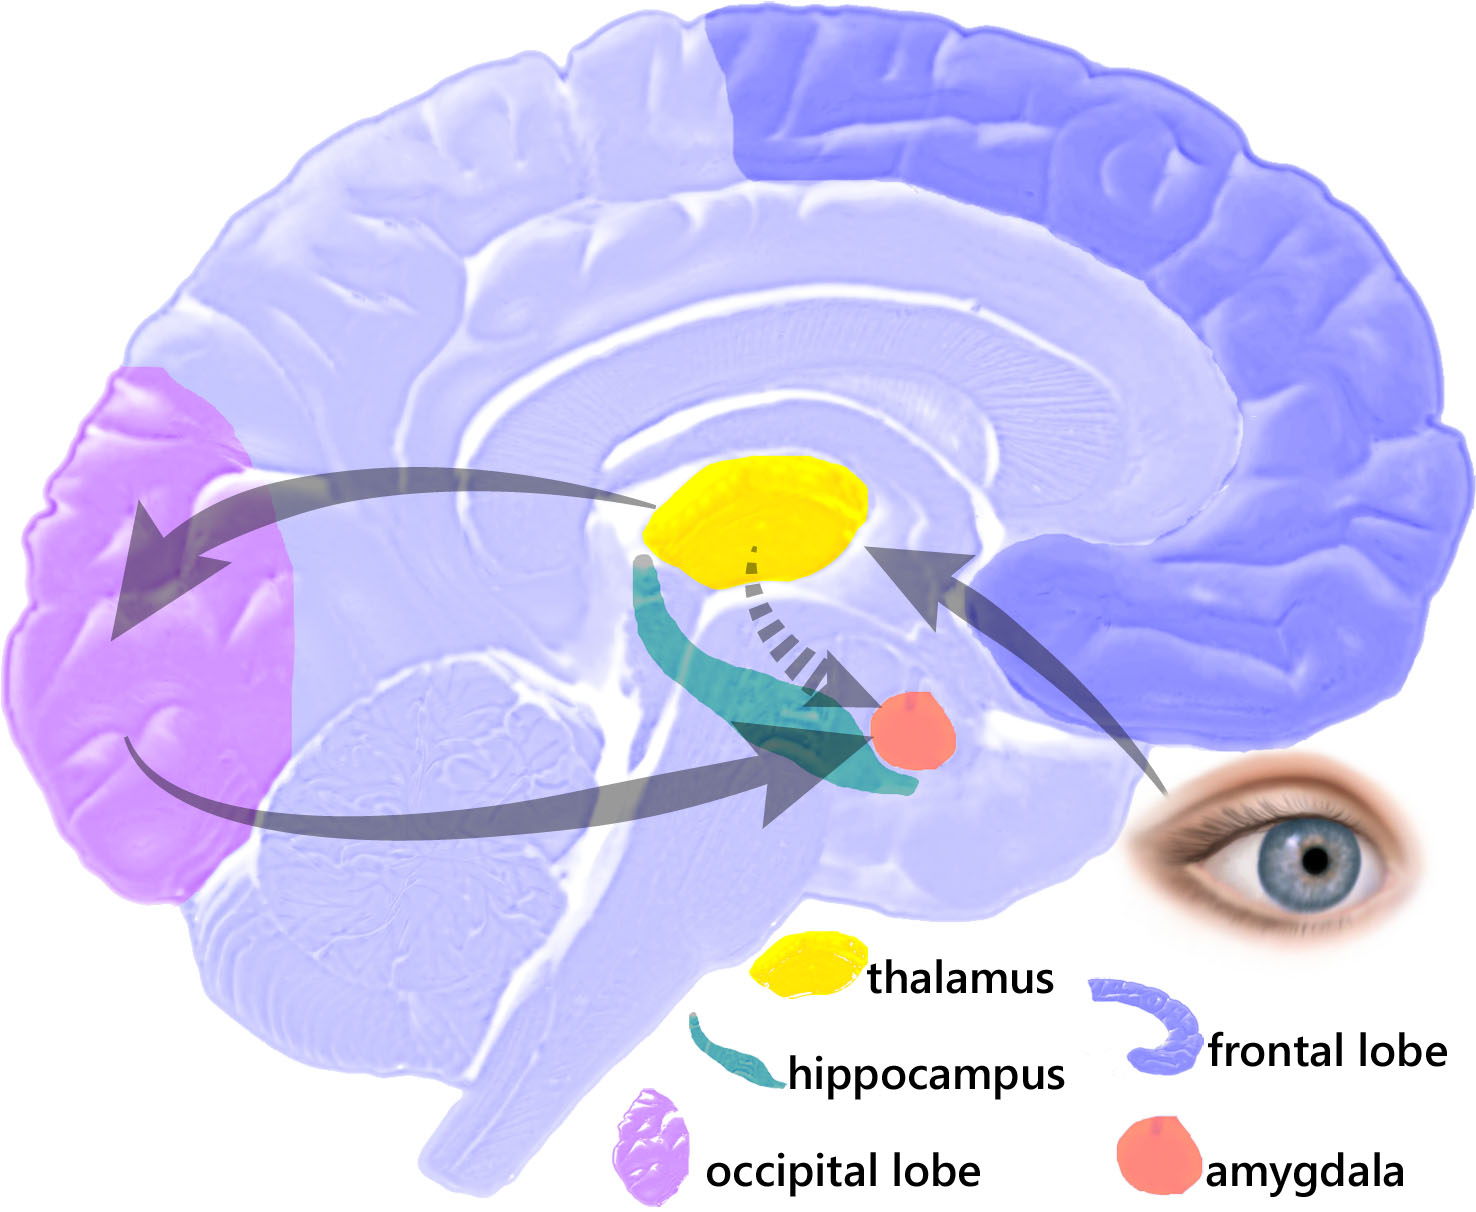

It's All in the Eyes: Amygdala's Role in the Experience and

Amygdala function in emotion, cognition, and behavior - ScienceDirect

The Cortex and the Amygdala - SOAR Library - SOAR

The Amygdala and Fear Conditioning

Beyond Emotion: Understanding the Amygdala's Role in Memory | Dana

PTSD, the Hippocampus, the Amygdala: How Trauma Changes the Brain

The Limbic System